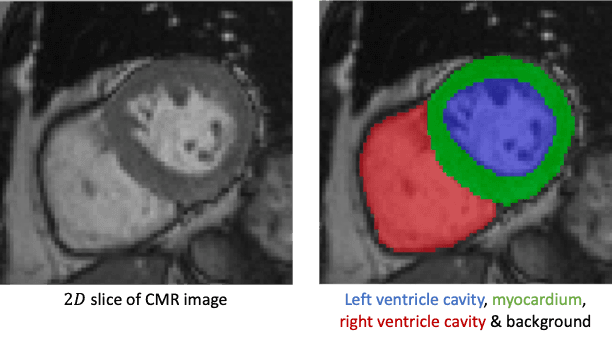

Custom model for left ventricle segmentation in cardiac MRI. Based on a Kaggle-style challenge (IMA205: Apprentissage pour l'image et la reconnaissance d'objets).